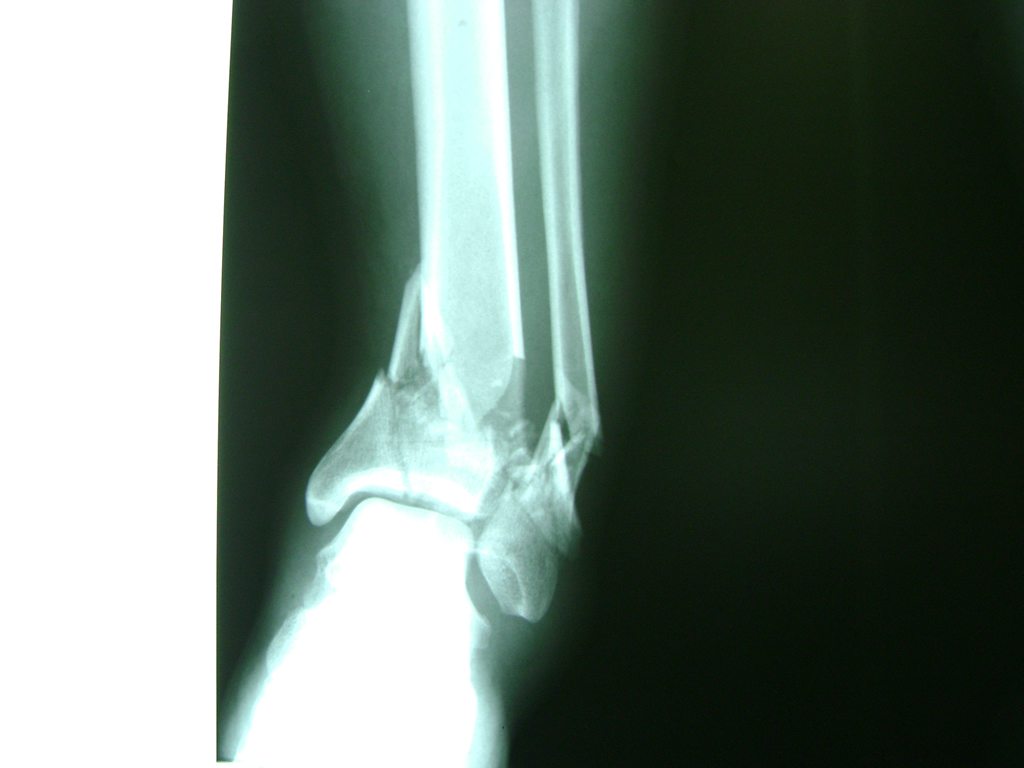

Una fractura de tobillo es la rotura de uno o más de los huesos del tobillo. Estas fracturas pueden ser:

- Completas (el hueso está perforado y está en 2 partes).

- Los extremos de los huesos están desalineados entre sí (desplazados).

- La fractura se extiende hasta la articulación del tobillo (fractura intra-articular).